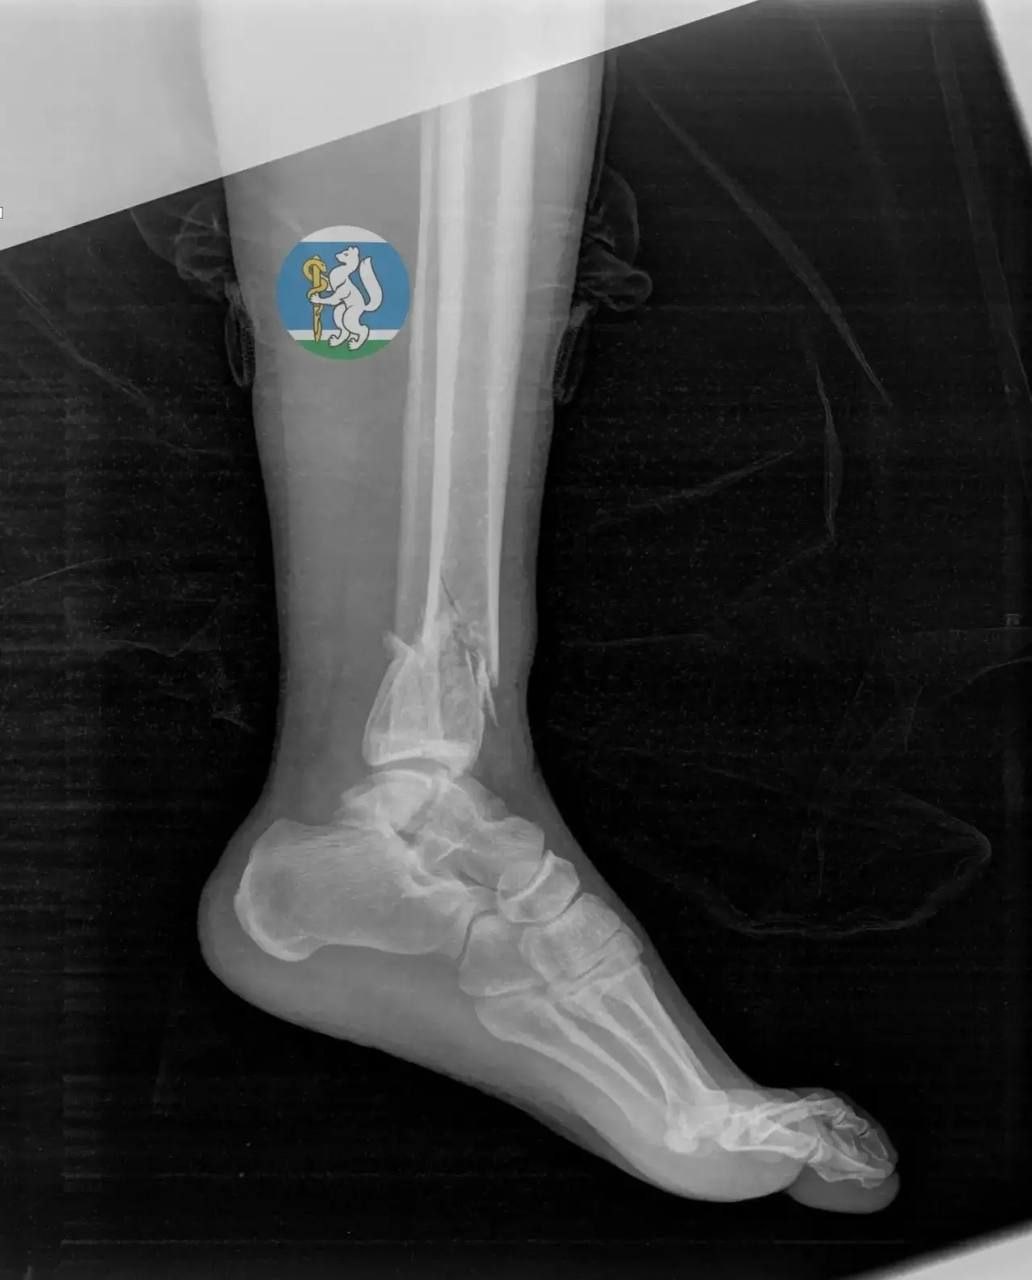

Женщина (36 лет) выпала во время мытья окна. Ее доставили в Городскую больницу №36, где диагностировали черепно-мозговую травму, повреждение позвоночника, множественные переломы таза и открытые переломы ноги – с такими травмами большинство пострадавших не доживают даже до приезда скорой.